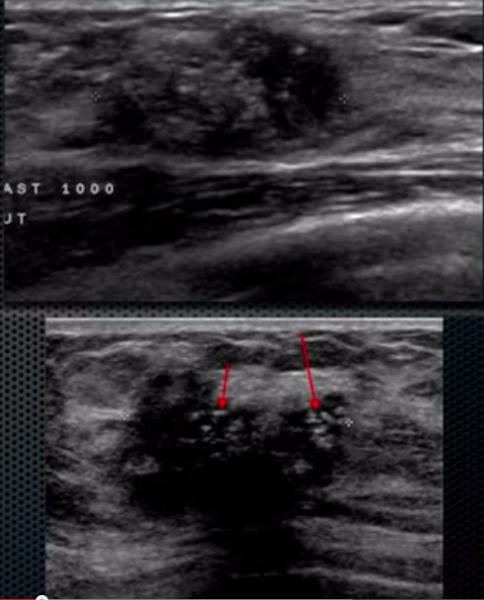

What is a Complex Cysts?

benign breast condition

contain some low level internal echotexture or intra-cystic debris.

Risk of malignancy among complicated breast cysts is thought to be 0.3-2%

What is the Sonographic Appearance of Complex Cysts?

Low to medium echogenicity

Irregular walls

hetertogenous

fluid filled levels

septations

wall thickening

debris

varying degrees of shadowing

What are the presentations of Complex Cysts?